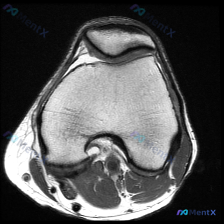

这是一份膝关节MRI T1序列轴位单张图像,核心疑问是评估是否存在「软骨异常」。

- 扫描层面是膝关节上部,主要显示髌股关节(髌骨+股骨滑车)和股骨髁

- 髌骨软骨下骨、股骨髁骨皮质轮廓清晰,骨松质信号均匀,没有看到局灶性骨水肿或骨折线

- 髌股关节间隙尚可,关节软骨面边缘轮廓相对规整,没有看到明确的软骨剥脱、严重缺损或变薄

- 关节腔内没有明显积液,滑膜没有增厚或结节样改变

- 髌旁支持带、周围皮下脂肪、腘窝前方软组织都没有异常信号

- 当前图像层面没有发现支持「软骨异常」的明确结构性影像学证据,髌股关节软骨形态基本正常